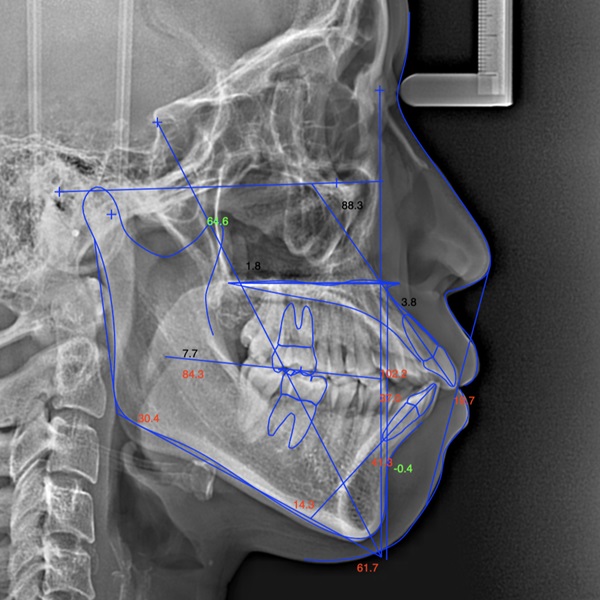

矯正前後の顔貌変化のシミュレーション参考写真

顔貌変化予測はセファロレントゲン分析や顔面写真を使った複雑な工程を複数のソフトウェアを駆使して行います。

※上顎前突(出っ歯)の患者さまの一例(小臼歯の抜歯を行った場合の予測)となります。

①矯正治療前の横顔 Eライン(※)

②セファロ(側方頭部X線規格写真)の分析

③各データからの横顔の矯正治療後予測 ※Eライン

※<参考>

横顔において、鼻とあごの頂点を結んだ線を『Eライン(エステティックライン)』と呼びます。人種などで多少の違いはありますが、Eライン上もしくは少し内側に上の唇が入る状態が、美しい横顔と言われています。上の患者さまでは矯正治療前にはEラインより上の唇が前に飛び出していますが、シミュレーション後ではEライン内に納まっています。

上のシミュレーションのように『口元を大きく下げたい』場合は上記の抜歯矯正が適応になることが多くなります。

小臼歯を抜かずに行う矯正(非抜歯矯正)でも多少口元を下げられることもありますので、ご希望をお聞かせください。

インビザラインは非抜歯矯正でも抜歯矯正でもどちらでも対応可能ですので、治療予測と患者さまのご要望を照らし合わせて計画を決めております。